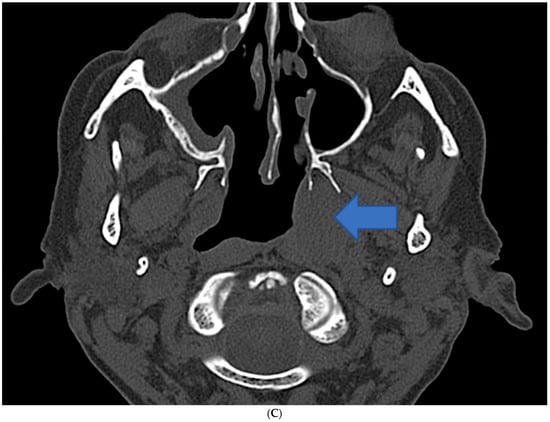

2.1. Case 1

2.2. Case 2

2.3. Case 3